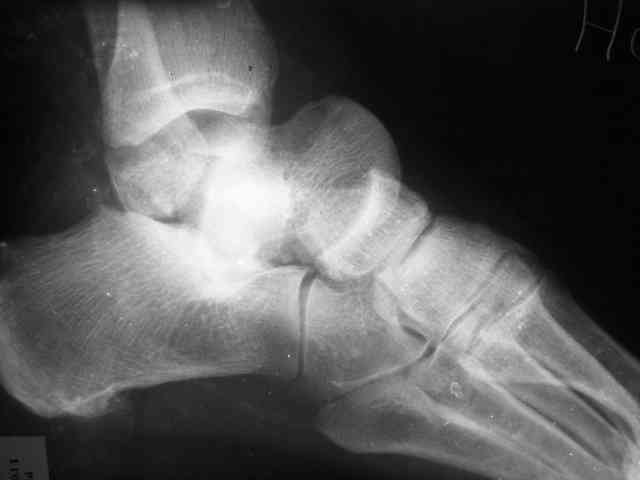

Re: Редкое повреждение - полный вывих тарана!

Уважаемый Александр! Как обещал представляю Р-граммы и операционные фото.